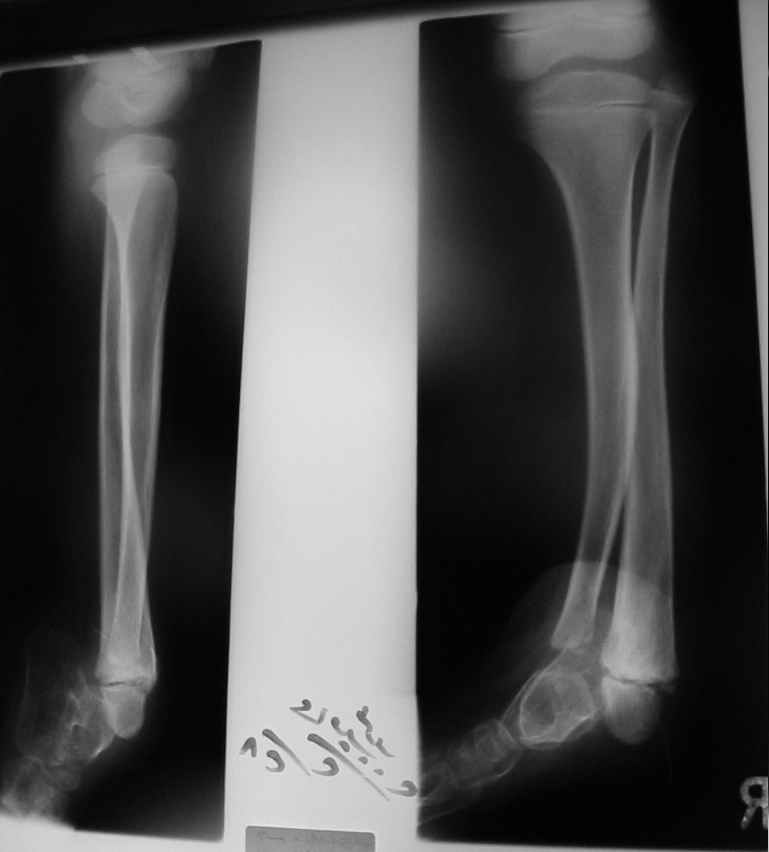

Судя по представленным фото и Рг граммам, у 13 летнего ребенка врождённая гемимелия большеберцовой кости, таранно-пяточный синостоз Из-за отставания в росте большеберцовой кости (остутствует дистальный эпифиз с зоной роста) произошла компенсаторная гиперофия малоберцовой кости, на которую приходится основная нагрузка (спонтанная тибиализация малоберцовой кости). Как результат дисбаланса осевого роста вторично возникла эквино-варусная деформация стопы. Продолжающийся рост ребёнка (до естественного закрытия зон роста) будет приводить к усугублению деформации по приведенным выше причинам.

Своё наблюдение только одно (ребёнка наблюдали и продолжаем наблюдать с рождения) и дважды оперировали: 1 этап выполнили проксимальный тиб/фиб фьюжн вторым этапом медиализация малоберцовой кости с таранно- малоберцовым синостозом и ещё предстоят этапы по удлинению тибиализированной малоберцовой кости.

В вашем случае я бы избрал следующую тактику:

Поднадкостничную остеотомию большеберцовой кости в средней трети с формированием синостоза с малоберцовой ( активно растущей) костью и второй уровень в области дистального тиб/фиб синдесмоза- достигается баланс роста( средне-медиальный и латеральный отделы) в области измененного голеностопного сустава. Коррекция эквино-варусной деформации стопы в аппарате после чрезкожной сегментарной тенотомии ахилова сухожилия. Дело

кропотливое и длительное.

Как резервный вариант может быть рассмотрена ампутация в верхней трети голени с изготовлением функционального протеза, если родители ребенка не настроены на длительную коррекцию и многоэтапную хирургию, родственники должны понимать, что абсолютного функционального результата даже после этапных операций достичь будет невозможно (аномальный голеностопный сустав, таранно-пяточный синостоз).